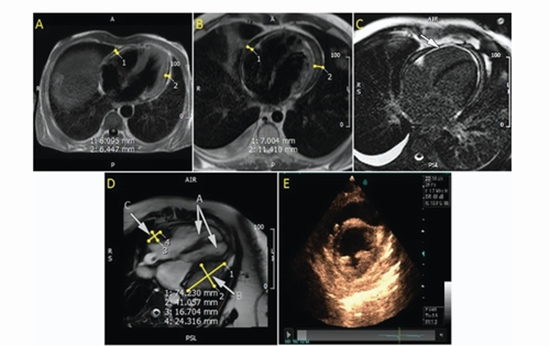

Diagnostic Efficacy of Magnetic Resonance Imaging and Echocardiography in Diagnosis of Constrictive Pericarditis

Diagnostic of MRI and Echocardiography in Constrictive Pericarditis {faces}